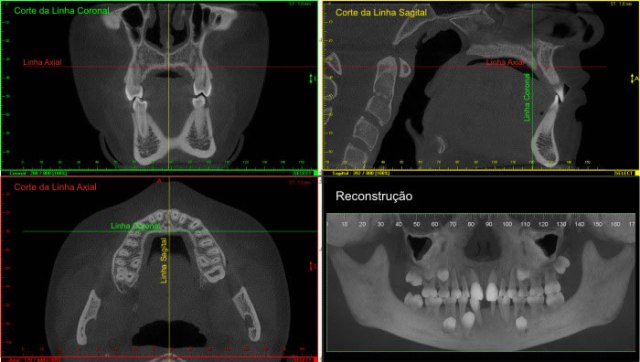

Na apresentação básica, a reconstrução do exame tomográfico aparece como fatias de imagens nos três planos: coronal, axial e sagital.

O radiologista “navega” por estas imagens, analisando toda a aquisição e com o auxílio de ferramentas ele monta e escolhe as imagens que irão compor o filme.

Nos softwares há ferramentas que permitem a reconstrução e a obtenção de novos cortes que mostram imagens de uso pontual na odontologia como os cortes transversais e longitudinais.

Os cortes transversais são cortes perpendiculares ao arco da maxila e mandíbula.

Na reconstrução panorâmica aparece uma régua no limite inferior que serve de localização para os cortes transversais.

Os cortes longitudinais são cortes no sentido vestíbulo lingual ou palatino, perpendiculares a uma reta traçada sobre o dente ou a área em questão.

Algumas orientações são necessárias para melhor entender as imagens tomográficas.